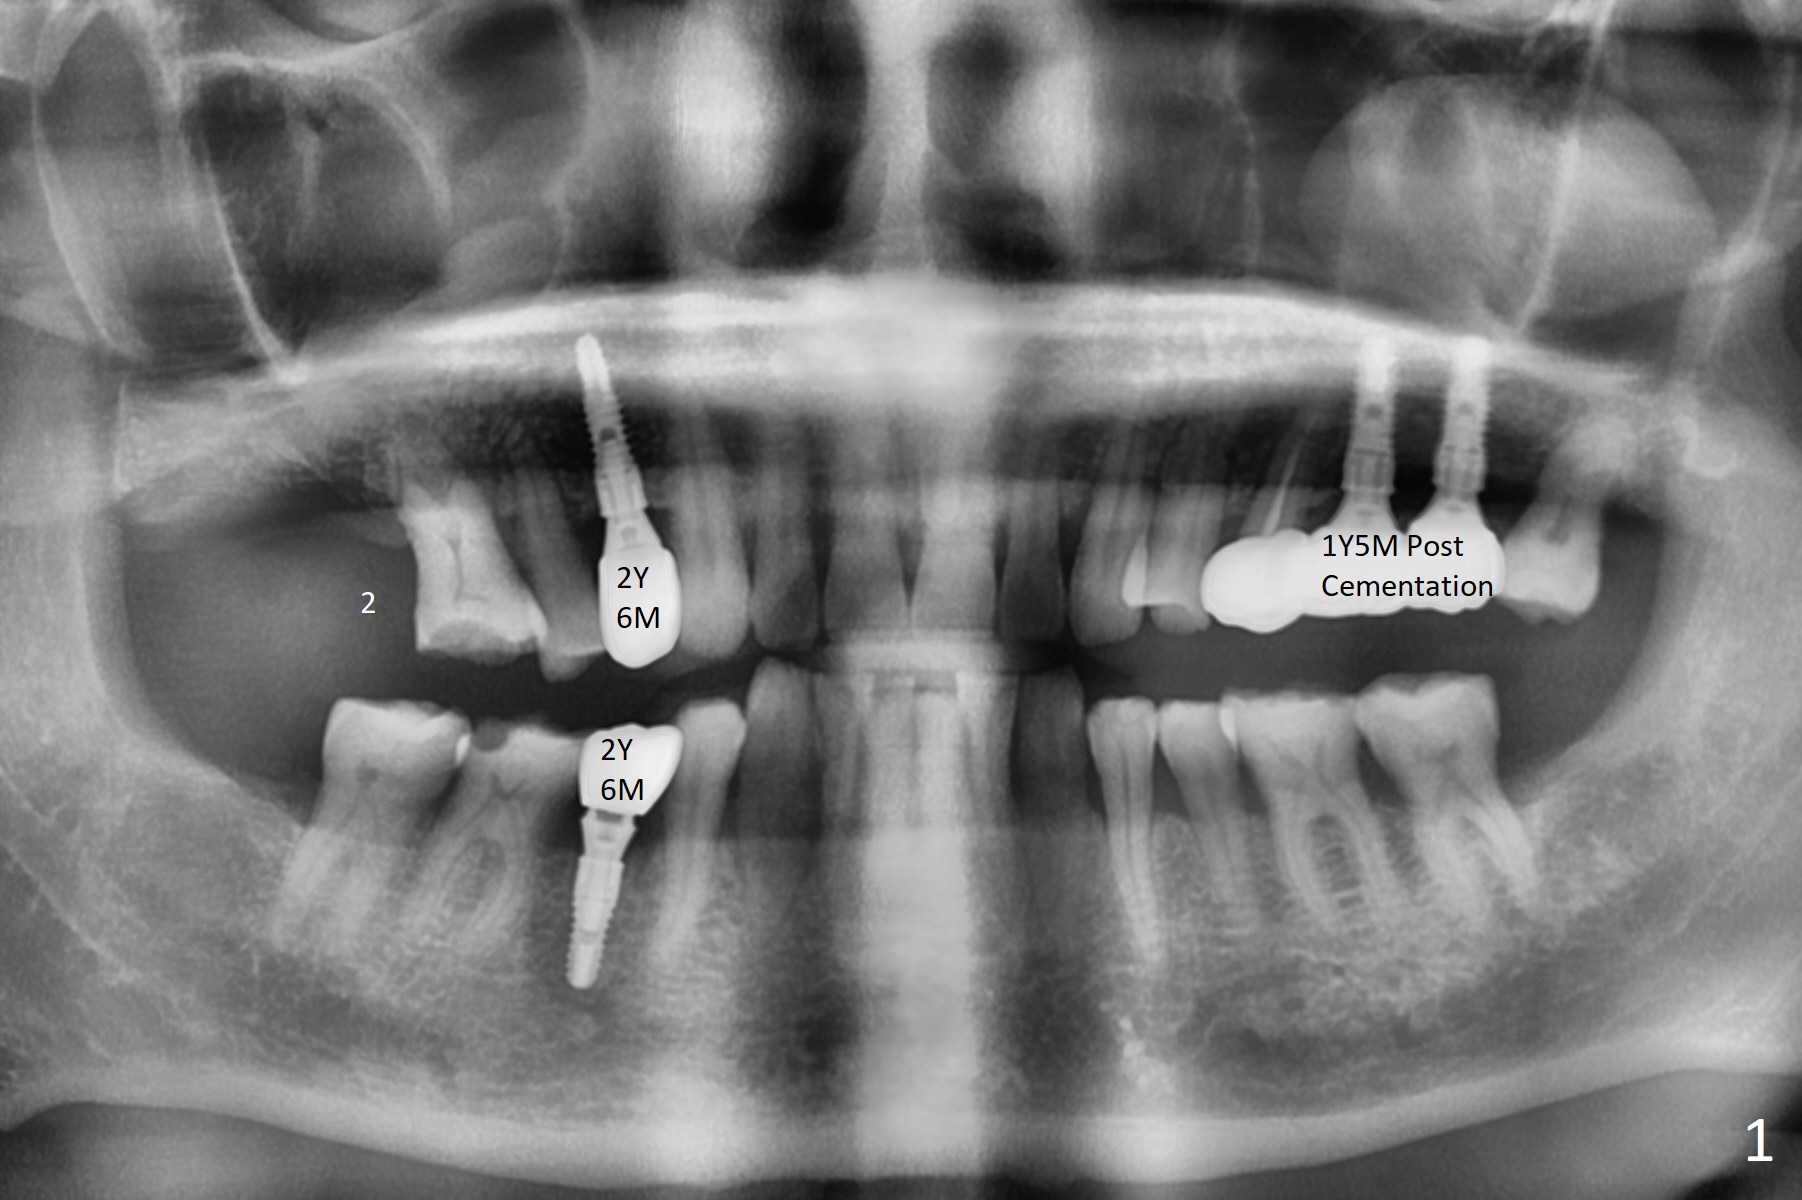

A 59-year-old man requests implant at #2 after those at #5, 14/15, and 29 (Fig.1). Sinus lift is required at #2 (Fig.2). Prepare PRF and SM implant (to be consistent with the previous ones without screw loosening). Although there is periapical radiolucency at #13 (Fig.3 >), there is another between #12 and 13 (Fig.3 *), which may be related to the apical infection at #12 (Fig.4 <).